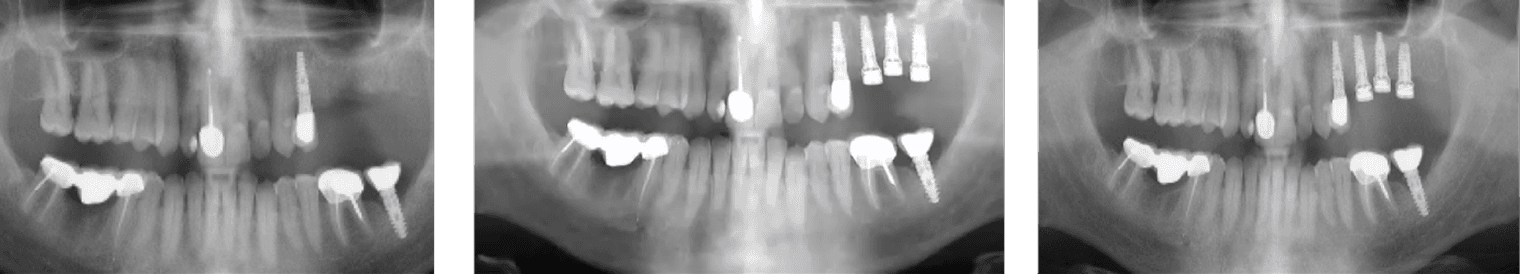

A 70-year-old heavy smoker presented with a fully edentulous mandible and clinically poor bone quality. Six implants were placed, each fitted with a MED healing abutment to enhance bone regeneration and support early osseointegration. Despite the compromised bone condition and smoking-related healing challenges, the patient demonstrated an excellent biological response throughout the recovery phase.

After only 45 days, radiographic assessment confirmed successful osseointegration across all six implants, allowing for full-arch prosthetic restoration. The patient received a stable mandibular bridge within a significantly shortened treatment period. The use of MED healing abutments contributed to rapid bone maturation, improved implant stability, and an accelerated rehabilitation process even in a high-risk, heavy-smoking patient.

A 73-year-old female patient with long-standing type II diabetes mellitus (average glucose level ≈ 200 mg/dL) presented with edentulism of the lower jaw and poor bone quality, classified as D4 bone - characterized by thin cortical plates and sparse trabecular bone. Seven implants were placed immediately after extractions, each equipped with a MED healing abutment to enhance bone metabolism and accelerate osseointegration, addressing the impaired healing potential typically associated with diabetic conditions.

Despite the compromised systemic condition and low bone density, the healing process was remarkably successful. Within less than three months, complete osseointegration was achieved across all seven implants, enabling delivery of the final prosthetic restoration. The use of MED healing abutments significantly improved local bone response, stabilized the peri-implant tissues, and facilitated rapid and predictable rehabilitation in a high-risk diabetic patient with D4 bone quality.